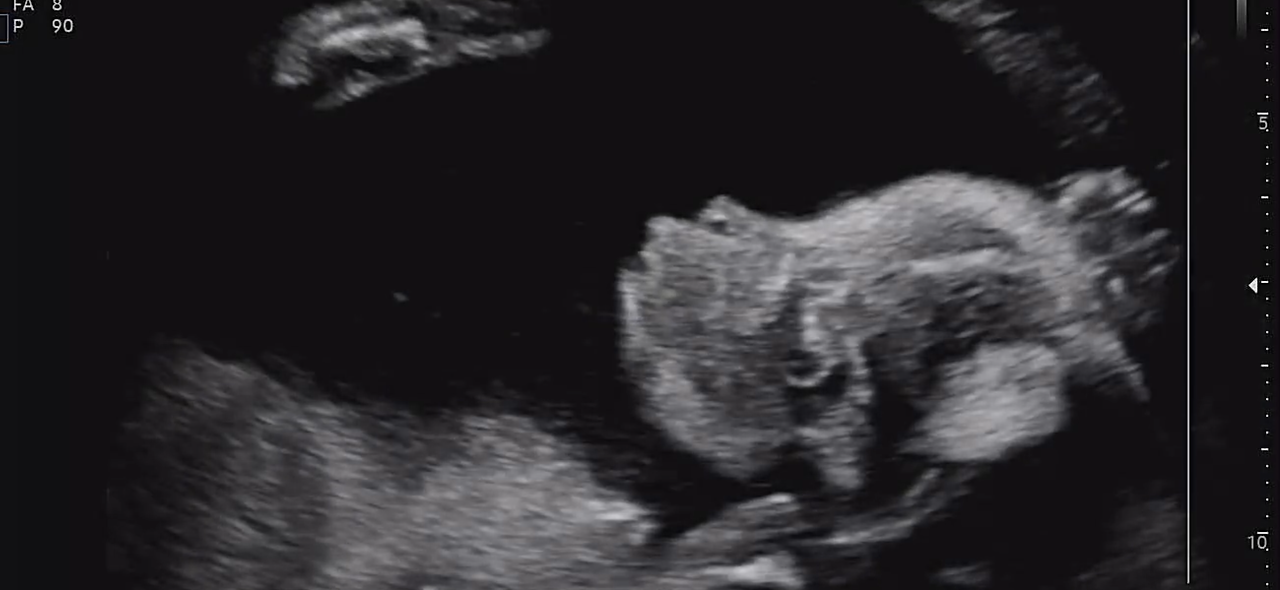

정밀 초음파는 생각보다 오래 걸렸다.

30분 가까이 이어진 검사 동안

손가락, 발가락, 귀, 콧구멍까지

아이는 하나하나 자세히 확인되었다.

22주 정밀초음파